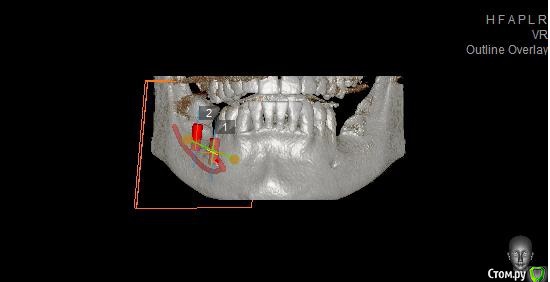

Павел7809 Опубликовано 21 ноября, 2017 Поделиться Опубликовано 21 ноября, 2017 Здравствуйте коллеги! Собственно ситуация на скринах. Для сосиджа как то экстремально большой объем. Блоки? Сетка?(ох как не хочется! последняя развалилась....) Крыша гаража? Из инструментария есть абсолютно все... Ссылка на комментарий

Чертков Александр Опубликовано 22 ноября, 2017 Поделиться Опубликовано 22 ноября, 2017 Горизонтальная остеотомия здесь не пойдет, форма гребня не располагает. Сетка или Цитопласт. Ну или 3Д по Кури...если владеете. Безусловно с удалением 8го. Короткие импланты в данной ситуации я бы не стал использовать. 3 Ссылка на комментарий

Павел7809 Опубликовано 22 ноября, 2017 Автор Поделиться Опубликовано 22 ноября, 2017 (изменено) Да, но проблема в том , что на место 7 ки как бы и 6мм не влезает. Вообще мысль появилась поставить короткую 6 ку на месте 6 го зуба, удалить 8, поставить на его место имплант(там с местом проблемы нет, и сделать мостик) . Ну или сетка(ой как не хочется!) Мало того я посмотрел и понял что элементарно влезают восьмерки в обл 36 38 Изменено 22 ноября, 2017 пользователем Павел7809 1 Ссылка на комментарий

колесников Опубликовано 22 ноября, 2017 Поделиться Опубликовано 22 ноября, 2017 Горизонтальная остеотомия здесь не пойдет, форма гребня не располагает. Сетка или Цитопласт. Ну или 3Д по Кури...если владеете. Безусловно с удалением 8го. Короткие импланты в данной ситуации я бы не стал использовать. гребень как гребень, делаете пропил за премоляром не вертикальный ,а косой и смещаете фрагмент мезиально по наклонной. 1 Ссылка на комментарий

Павел7809 Опубликовано 23 ноября, 2017 Автор Поделиться Опубликовано 23 ноября, 2017 гребень как гребень, делаете пропил за премоляром не вертикальный ,а косой и смещаете фрагмент мезиально по наклонной.Тоесть как то так? Ссылка на комментарий

Павел7809 Опубликовано 23 ноября, 2017 Автор Поделиться Опубликовано 23 ноября, 2017 Так,но я немного другое имел ввидуТо есть если я сделаю такие распилы подниму вверх и щечно то будет нормально? Ссылка на комментарий

Павел7809 Опубликовано 25 ноября, 2017 Автор Поделиться Опубликовано 25 ноября, 2017 Пообщался с пациентом. Сошлись на коротышках 4 на 6 в область 7 ки, 9 на 4 в области 6 4ки. Да и по факту я посмотрел - коронки не будут такими уж огромными выглядеть. 1 Ссылка на комментарий